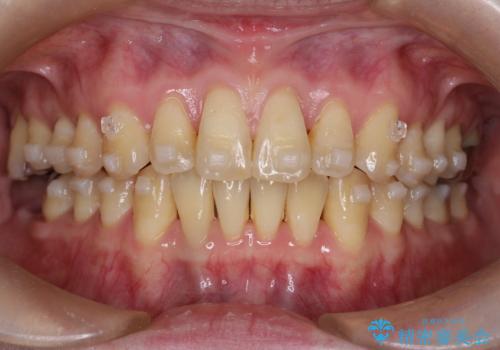

【インビザライン】前歯の捻れとオープンバイト

- 上の前歯の捻れと、前歯で物が噛めないことを主訴に来院されました。

前歯の翼状捻転とオープンバイト傾向だったため、インビザラインにて矯正を行いました。右下の奥歯は保存不可だったため、抜歯を行いインプラントにて修復を行なっています。

翼状捻転はインビザラインでは苦手とする動きですが、ここまで綺麗に治すことができました。